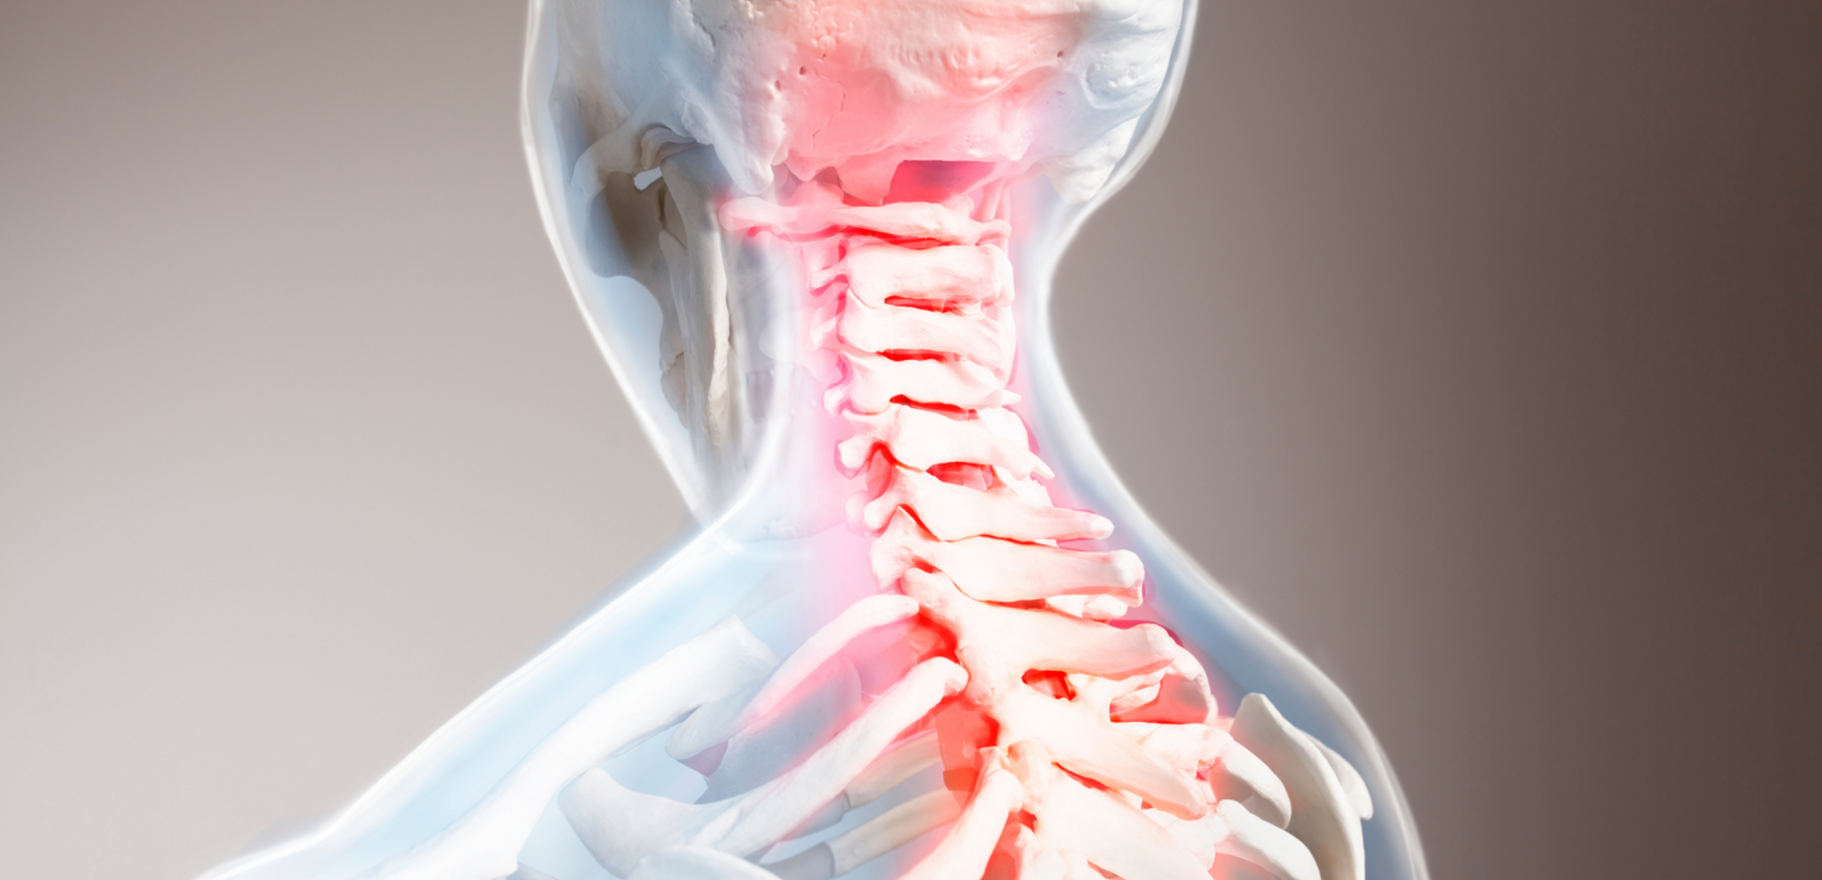

Кривошея (тортиколлис) — это состояние, при котором голова пациента наклоняется в одну сторону, а шея и мышцы становятся напряжёнными, что приводит к болям и ограничению подвижности. Это заболевание может быть врожденным или приобретённым, и его лечение направлено на устранение болевого синдрома, восстановление нормальной осанки и улучшение подвижности шеи. В зависимости от формы тортиколлиса, лечение может включать медикаментозную терапию, физиотерапию или, в некоторых случаях, хирургическое вмешательство.

- При хронических болях в шее, когда наблюдается устойчивое напряжение и спазм мышц.

- При ограничении подвижности шеи, когда наклон головы становится болезненным и нарушает нормальную осанку.

- При наличии симптомов, таких как головокружение, головные боли, проблемы с дыханием, что может возникать при длительной компрессии нервных корешков.